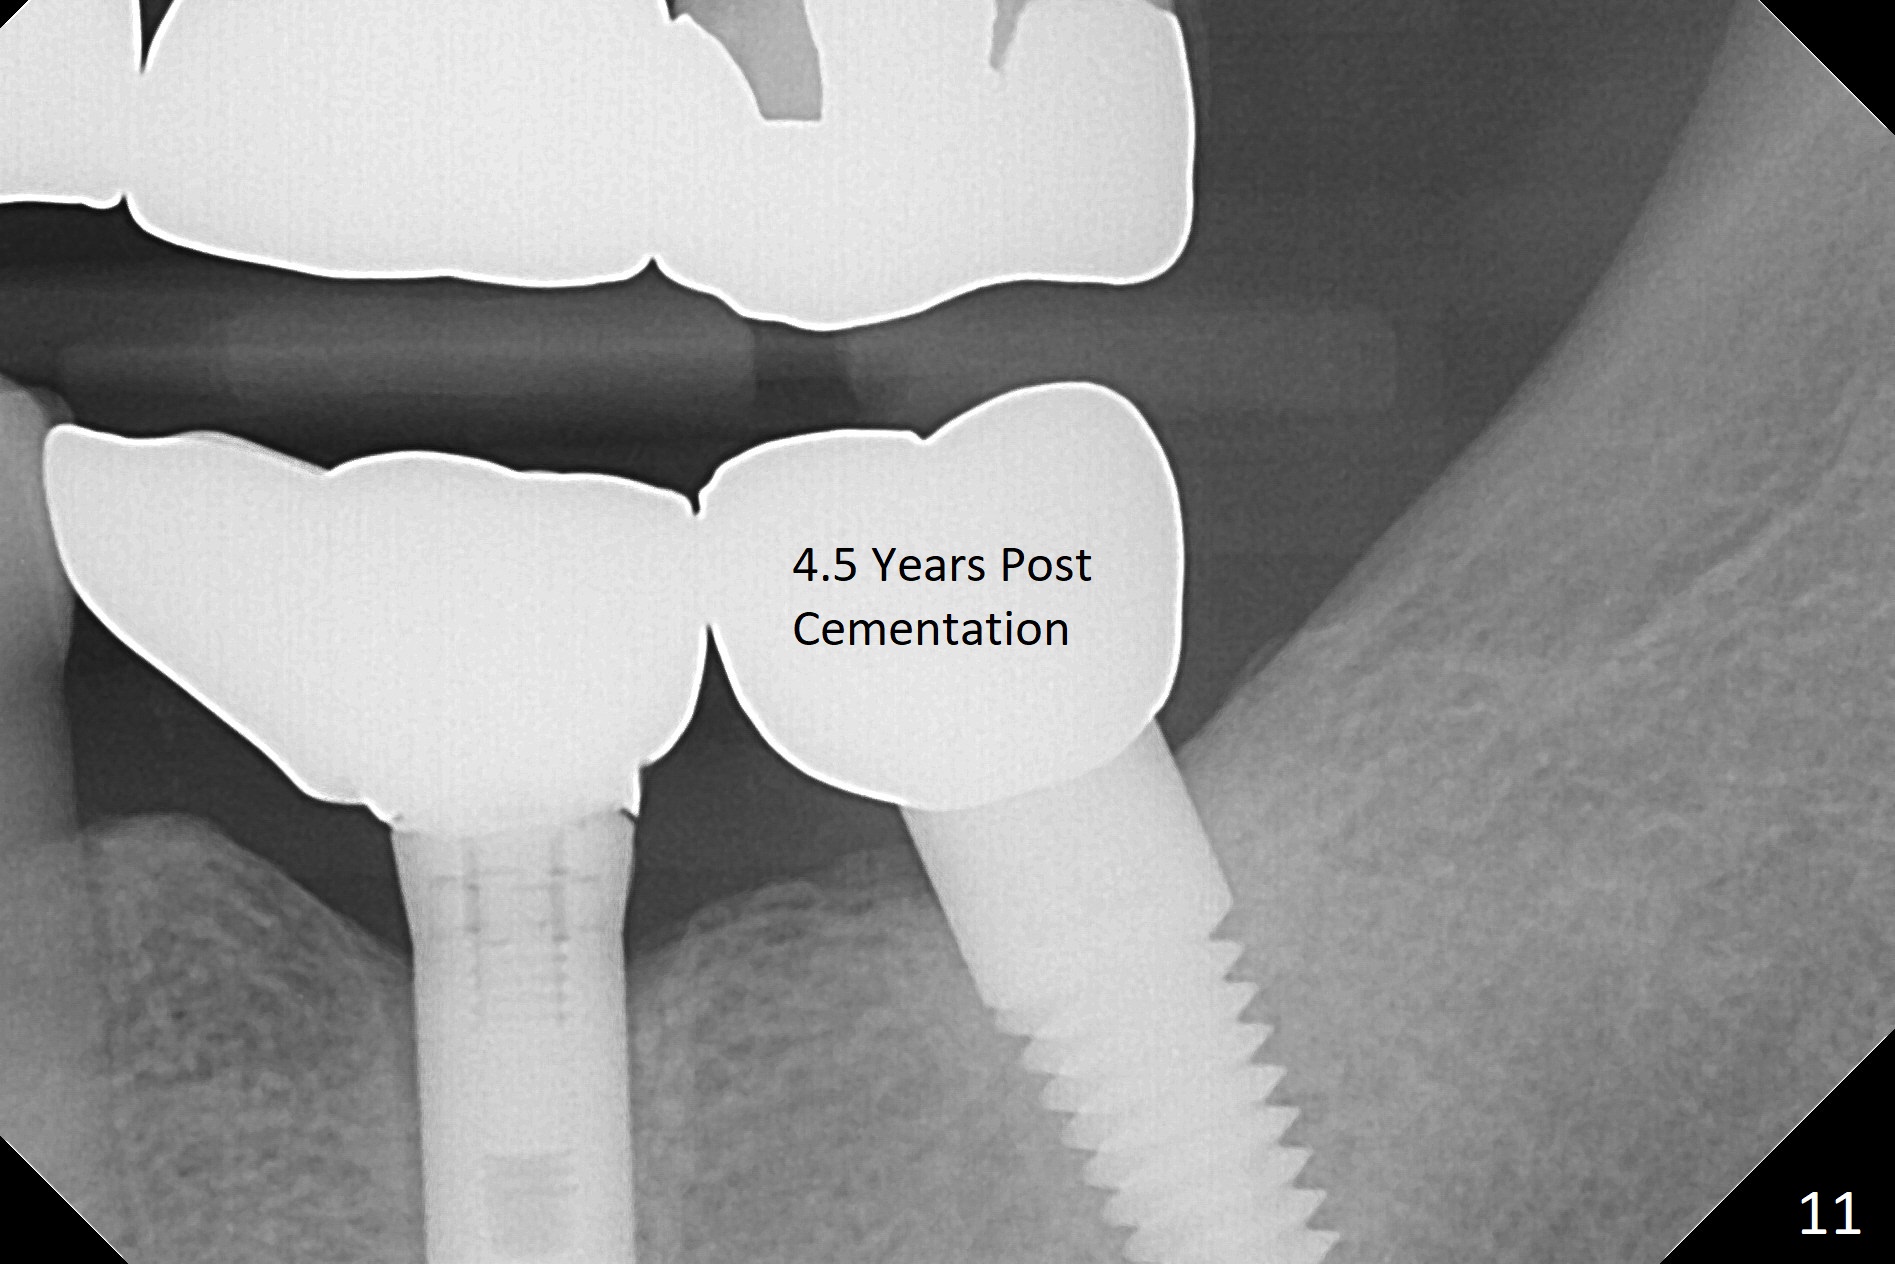

A 69-year-old man needs an implant at #18 (Fig.1,2 CT (sagittal and coronal sections)). In spite of use of surgical stent, the trajectory is not ideal (Fig.3-5). The following day the implant is removed with bone graft (Fig.6). In the 2nd placement, the trajectory is adjusted in each step (Fig.7-9 arrows) with long term stability (Fig.10,11).